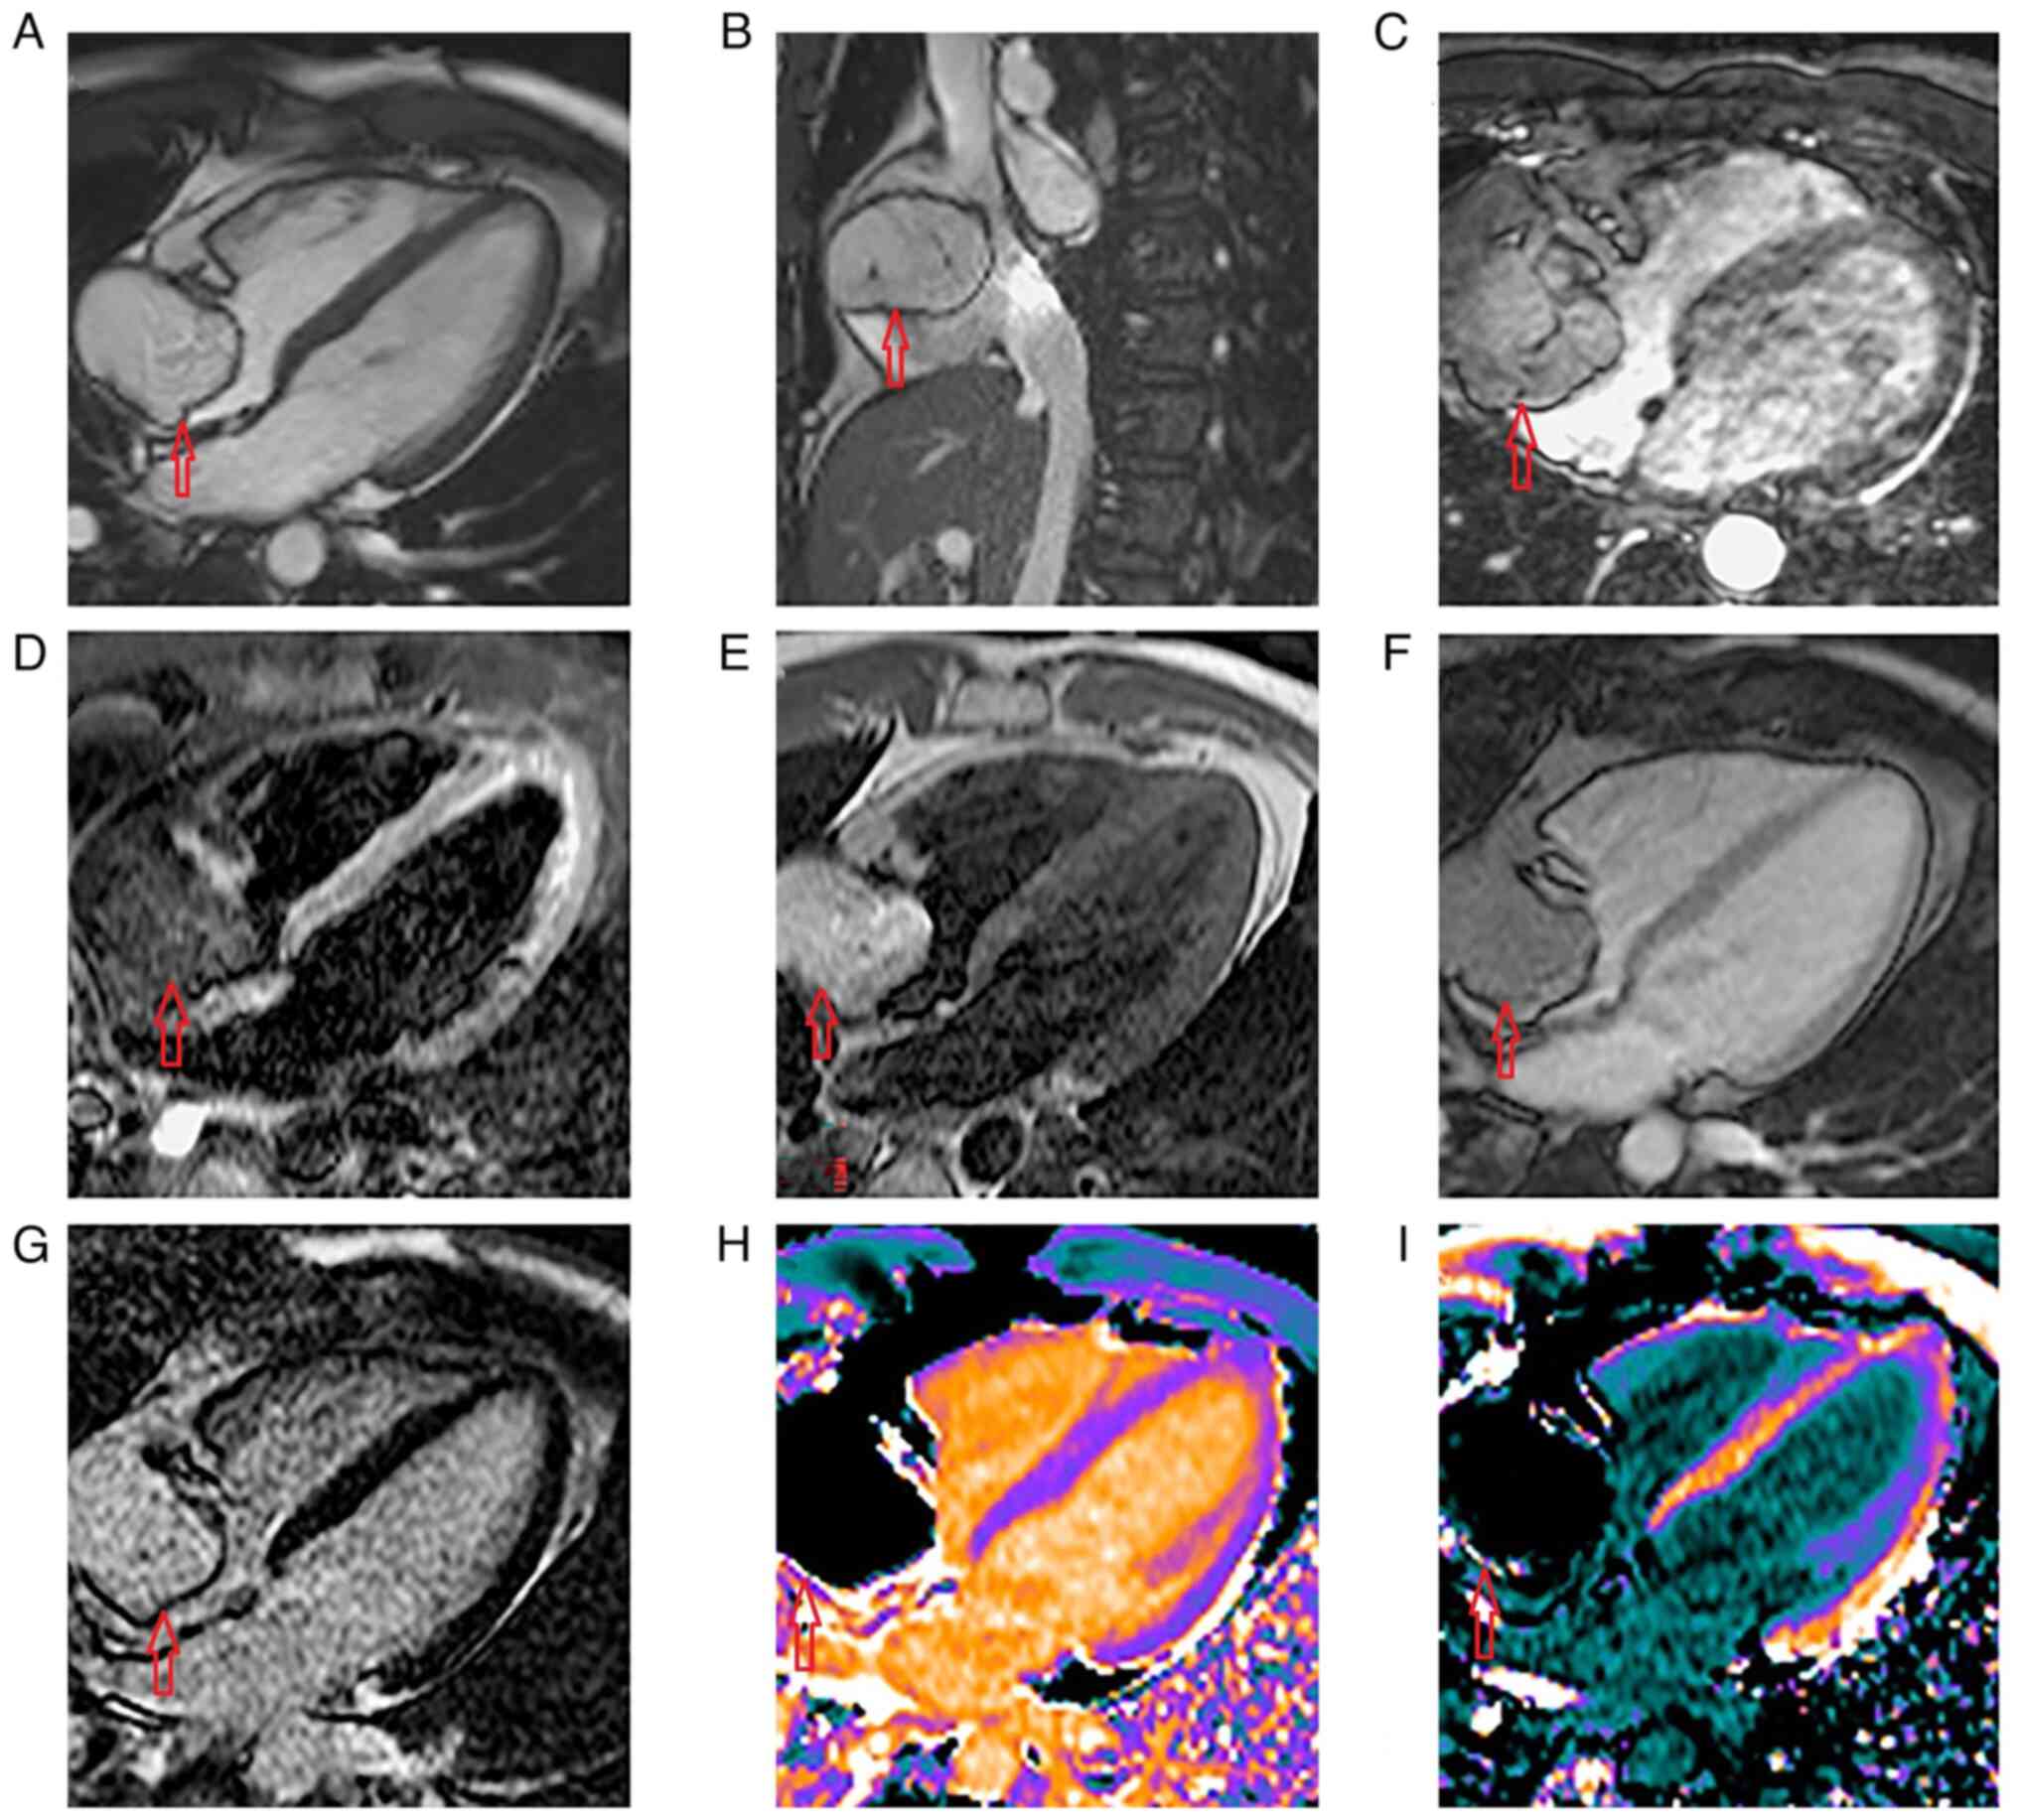

Right atrial lipoma: A case report and literature review

Cardiac lipomas are generally asymptomatic even in large dimensions. Echocardiograms can identify tumors, but cardiac magnetic resonance imaging or cardiac computerized tomography can differentiate cardiac lipomas from other cardiac tumors. The present study is a case report of an asymptomatic 30‑year‑old man diagnosed with atrial lipoma. The patient received cardiac surgery and the intervention consisted of exclusion of the right atrial (RA) tumor and reconstruction of the right atrium with ‘XenoSure’ patch in extracorporeal circulation through a minimally invasive approach. A short PubMed literature review was performed and 26 cases of RA lipomas with available details were found. Cardiac tumors may cause clinical presentation through different pathways. Symptoms related to an RA lipoma were present in 21 out of 26 patients (80%). The symptoms varied greatly, dyspnea being the most common of them. In one case, the lipoma was found during the autopsy of a patient after sudden death. Large cardiac lipomas can lead to complications such as obstruction of ventricular outflow tract, electric disorders, embolism or pericardial effusion. Obstruction of the right ventricular outflow tract was reported in 11 out of 26 patients (42%) diagnosed with RA lipoma. Generally, atrial lipoma can have various sizes. The most useful imaging technique was transthoracic echocardiography. Accurate diagnosis and evaluation of cardiac lipoma is dependent on multimodality imaging methods, including cardiac magnetic resonance. Surgery is the treatment of choice, but the risk‑benefit ratio must be considered, and shared decision making must be taken into account. The present review data showed that 23 out of 25 patients (92%) underwent surgery. Among these patients, only 1 out of 23 received a minimally invasive approach in 2021. Cardiac lipomas are rare entities, usually asymptomatic, that can occur at any age. The most useful diagnostic method of cardiac tumors is echocardiography, but nuclear magnetic resonance can also specify the type and characteristics of tumors.